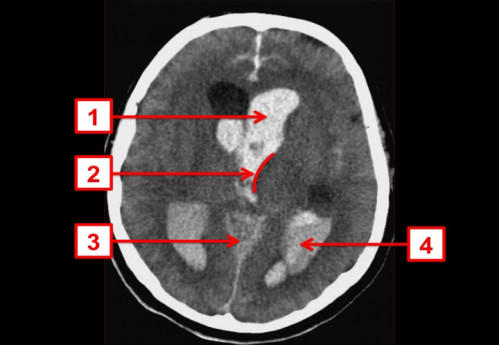

ICD: G91.9

ICD: G93.2

ICD: I61.5

ICD: I61.9

ICD: R40.2

64-jähriger Mann. Nachdem er heute Nachmittag fürchterliche Kopfschmerzen bekommen hatte, wollte er sich kurz hinlegen. Als die Ehefrau ihn nach zwei Stunden zum Abendessen holen wollte, schaffte sie es nicht ihn aufzuwecken und rief daraufhin sofort den Notarzt. Dieser findet beim Eintreffen einen Patienten mit einem Glasgow-Coma-Score (GCS) von 5 Punkten vor. Er entscheidet sich zur Intubation und verbringt den Patienten zügig in eine geeignete Klinik.